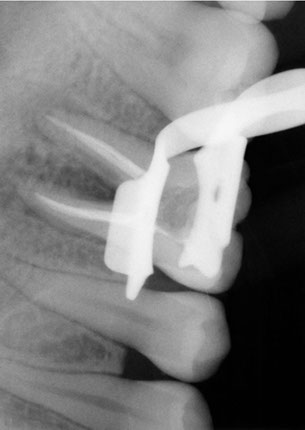

La endodoncia le da más tiempo de vida útil a su pieza dental, en Dental Evolution Cancún le recomendamos evitar la extracción realizándose este procedimiento que garantizamos será sin dolor, gracias a la tecnología de vanguardia con la que contamos, instrumental rotatorio, sistema de ultrasonido, y a nuestra “radiografía digital” la cual juega un papel crucial en el procedimiento de endodoncia, además de que usted estará atendido con la calidez, calidad humana y profesionalismo que caracteriza a nuestro experto equipo de dentistas especializados que le apoyaran en todo momento.